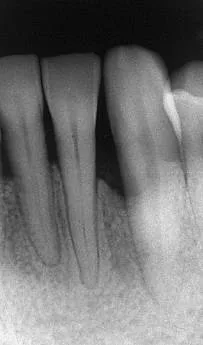

Des biomatériaux de synthèse seront utilisés afin de regagner, quand cela est possible, l’os partiellement détruit par la parodontite.

Des techniques chirurgicales de préservation papillaire permettent de régénérer les tissus parodontaux en garantissant leur maintien esthétique. Ces techniques chirurgicales avancées s’effectuent sous aides optiques grossissantes et avec des instruments micro chirurgicaux spécifiques.

Avant l’intervention

Quelques semaines après l’intervention